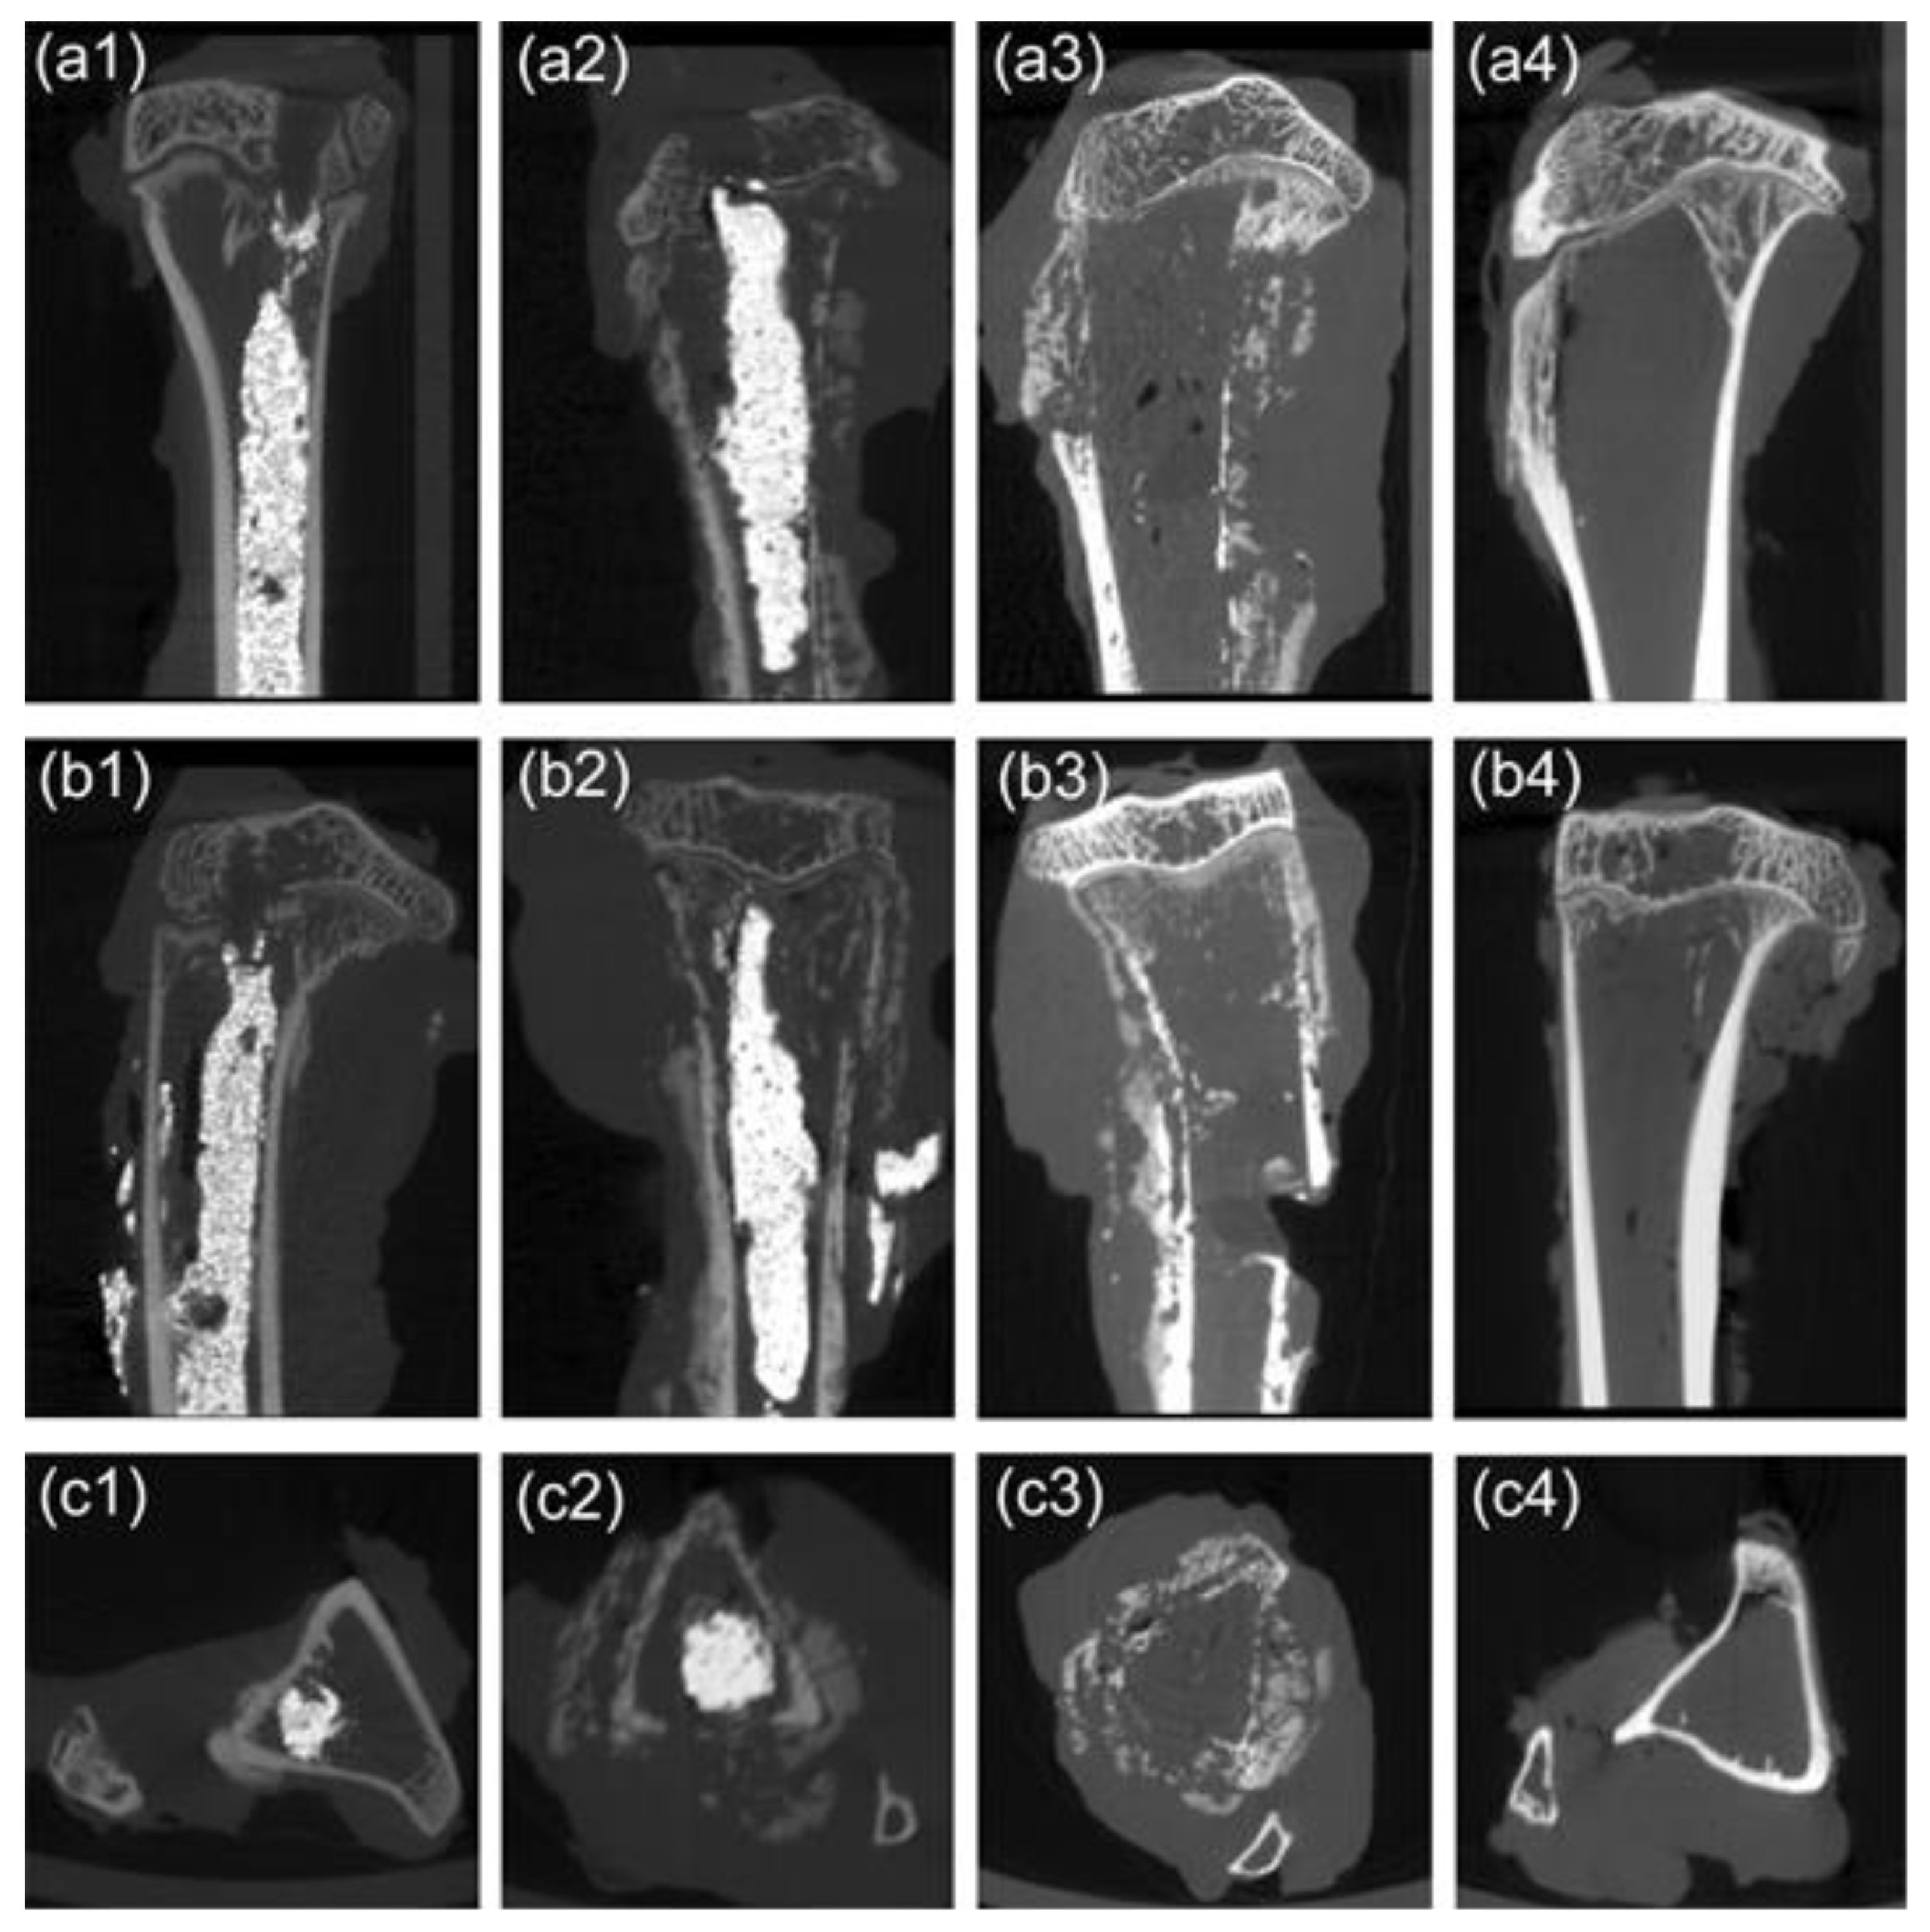

We further evaluated bone resorption using X-ray and micro-CT scans. The X-ray image was first roughly examined using the morphologic changes of the tumor-bearing tibias. As shown in Figure 5, with the pre-injection of M-PMMA, the cortical bone thicknesses and trabecular separation of the tumor-bearing proximal tibias were similar to the healthy hind legs in the three groups (Figure 5a1,b1,c1). Post-injection of M-PMMA, high-density bone cement was located in the cavum medullare of the tumor-bearing proximal tibias (Figure 5a2,b2). The volume of M-PMMA was calculated before injection (0.7–1.0 mL). At the end of the magnetic treatment, the tumor-bearing proximal tibias of rabbits in the M-PMMA and control groups were severely destroyed, and the surrounding soft tissues were swollen (Figure 5c1,c2), while those in the M-PMMA + AMF group were less damaged (Figure 5c3). Although thinning of the cortical bone was observed, the tibial shape was well maintained in the M-PMMA + AMF group.

Figure 5. X-ray images of the animal models. Images of hind legs in the M-PMMA + AMF group pre-injection (a1), after (a2) magnetic bone cement injection, and at the end of magnetic hyperthermia (a3). Images of the M-PMMA group (b1b3) and the control group (c1c3) at the same time point.